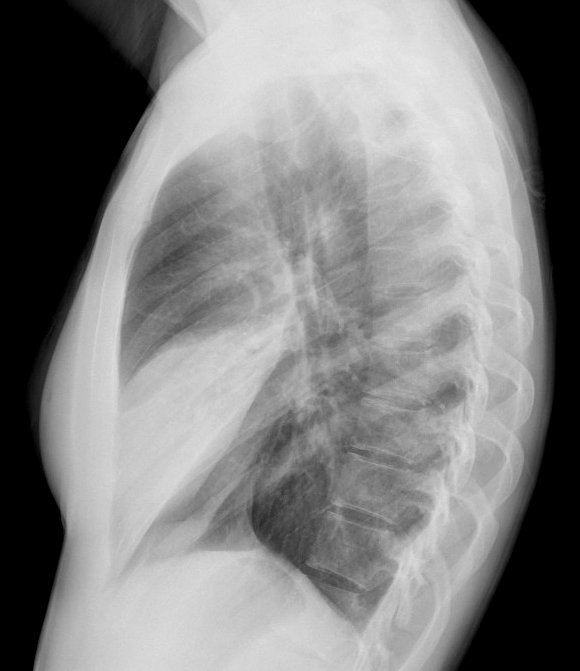

Gallery Pneumonia Case 4 RML pneum Lat

Case 4 RML pneum Lat